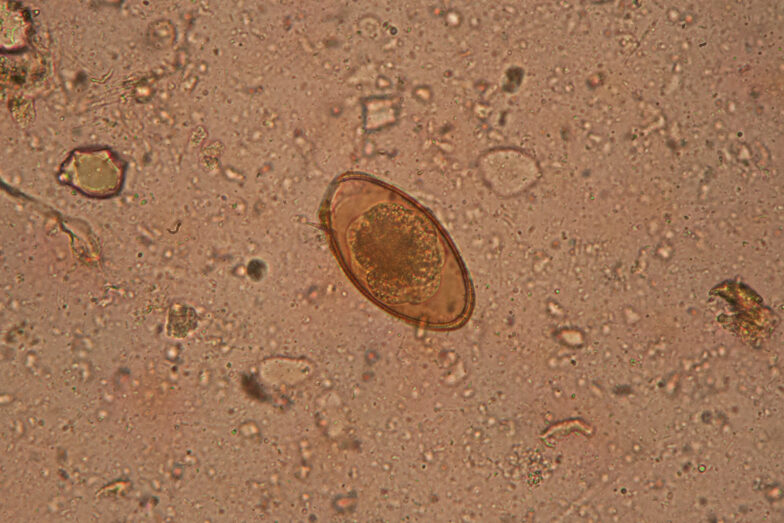

Leider konnten bei keinem der weiblichen Chamäleons die Geschlechtsorgane für die Studie beurteilt werden, da sie entweder krankhaft verändert oder mittels vorangehender Operation bereits entfernt worden waren. Als Ankopplungsort für den Ultraschall der Nieren stellte sich bei den Chamäleons eine seitliche Ankopplung etwa einen Zentimeter vor der Hüfte als günstig heraus. Der postpelvine Anteil der Nieren war stets kleiner als der präpelvine. Die Nieren wiesen bei allen männlichen Chamäleons heterogene Flecken auf, während die Nieren der Weibchen stets homogen waren. Diese Streifung ist vermutlich auf Sexualsegmente in den Nieren bei Männchen zurückzuführen. Das Nierengewebe war isoechogen zu Muskelgewebe und hypoechogener als Fettgewebe. Die Hoden der männlichen Chamäleons lagen jeweils im hinteren Drittel der Coelomhöhle direkt unter der Wirbelsäule und vor den Nieren. Der rechte Hoden lag jeweils etwas weiter vorne als der linke. Die Kapsel war bei allen Männchen hyperechogen, während die Hodenstruktur stets homogen war. Durchschnittliche Maße der Nieren und Hoden der Jemen- und Pantherchamäleons werden in der Studie ebenfalls angegeben.